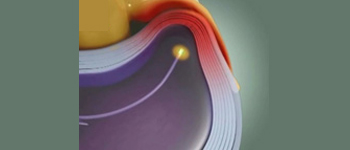

![]() |

고주파열치료술 가느다란 열선을 디스크 안으로 삽입하여 돌출 부위를 가열하여 디스크 주변의 통증을 유발하는 신경을 차단하고 디스크 벽을 수축시켜 튼튼하게 만드는 치료입니다. |